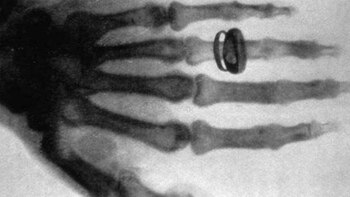

En el caso del autor de ‘Tradiciones Peruanas’, se pueden ver sus dedos torcidos y un anillo puesto en el meñique. La toma fue tomada cuando el escritor ya tenía 63 años de edad. Y así fue como la radiología hizo su debut en nuestro país y en toda Sudamérica.